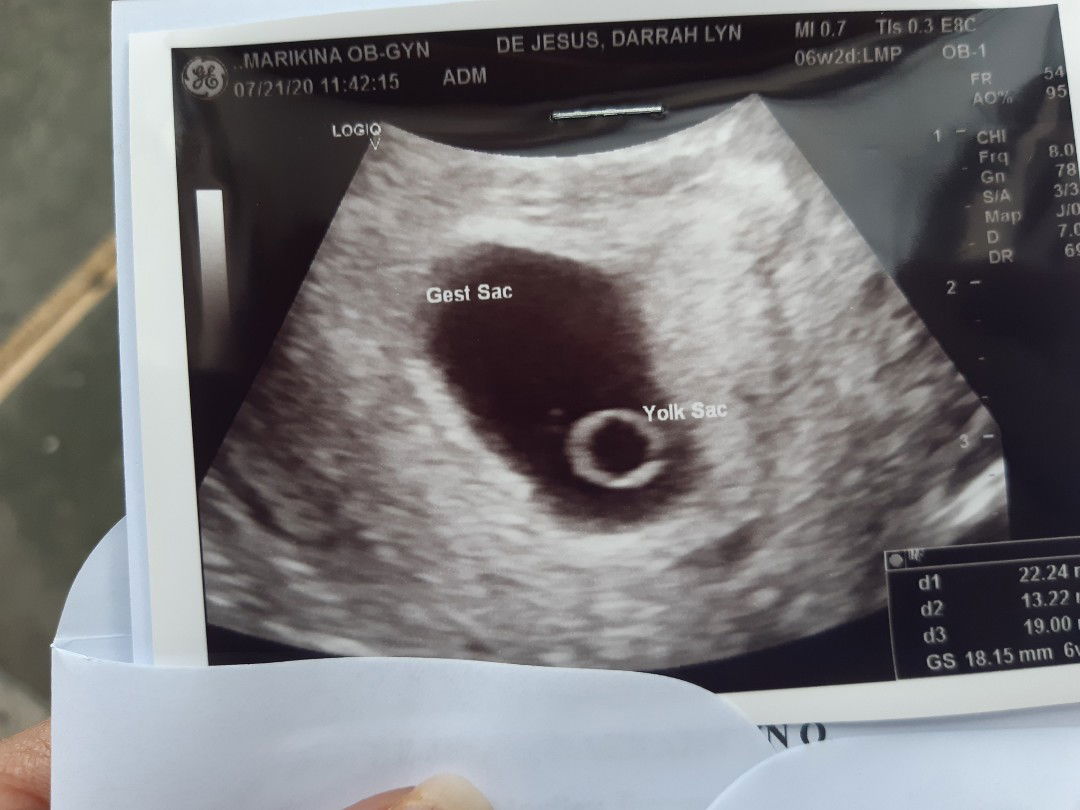

6weeks and 6days spotting mom here

Anyone here na nakasurvive sa spotting time of pregnancy. Worried lang. Pero ngpacheckup na aq and normal naman daw mahina lang kapit kaya may bleeding umiinom na din aq ng pampakapit and vitamins prescribed by my OB..